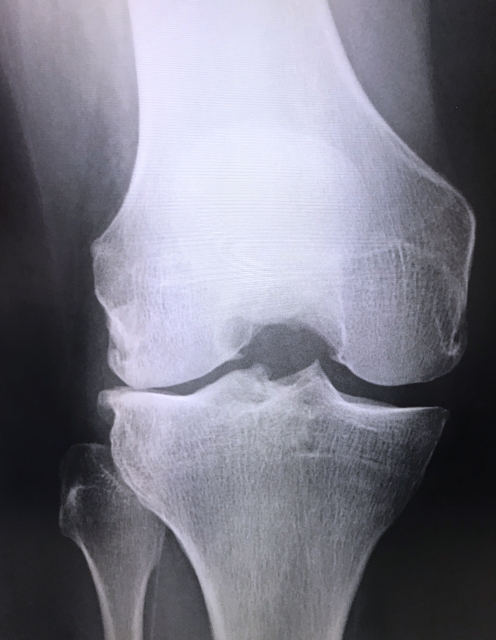

今回は、「本当に軟骨の変性だけ?変形膝関節症について」と言うテーマでお伝えします。

『膝関節において、関節軟骨の性質に異常をきたす疾患』です。

変性した軟骨は摩耗し関節内に遊離することで、関節の裏打ち構造をする滑膜に炎症(滑膜炎)を惹起し、滑膜水腫や滑膜肥厚などを誘発します。

一般的に,軟骨の衝撃を和らげる作用、軟骨下骨(軟骨の下にある骨)への力学的負荷の増大を招くことで、その中心部での硬化や辺縁部での骨棘形成などを誘発します。

これらの症状は緩やかに進行して行き、結果関節全体の構造が変化し膝の痛みなどの機能障害をきたします。

関節軟骨の変性と摩耗が主な原因とされていましたが

半月板や軟骨下骨,骨棘、そして滑膜も今まで以上に病態に関与することが明らかとなってきています。

変形性膝関節症における骨棘は、一般的に関節軟骨の摩耗による軟骨下骨への過剰刺激が誘因となり、荷重面を増加させるための反応により生じるとされていましたが、近年膝 OA 患者の 日常生活動作の低下の増悪因子とされています。

関節変形について

関節軟骨や軟骨下骨の摩耗が局所的に生じると関節の変形が起こります。

日本では内側に多く生じることが多いとされており、よく『膝の内側が痛い』と訴えられることがあります。